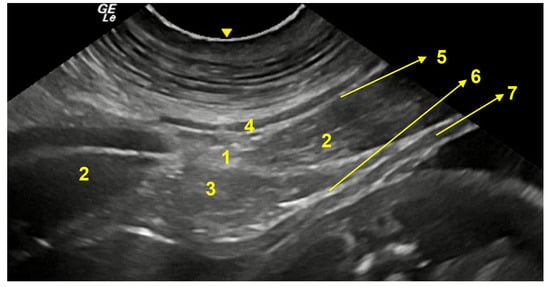

3.3. Ventral Abdominal Ultrasound